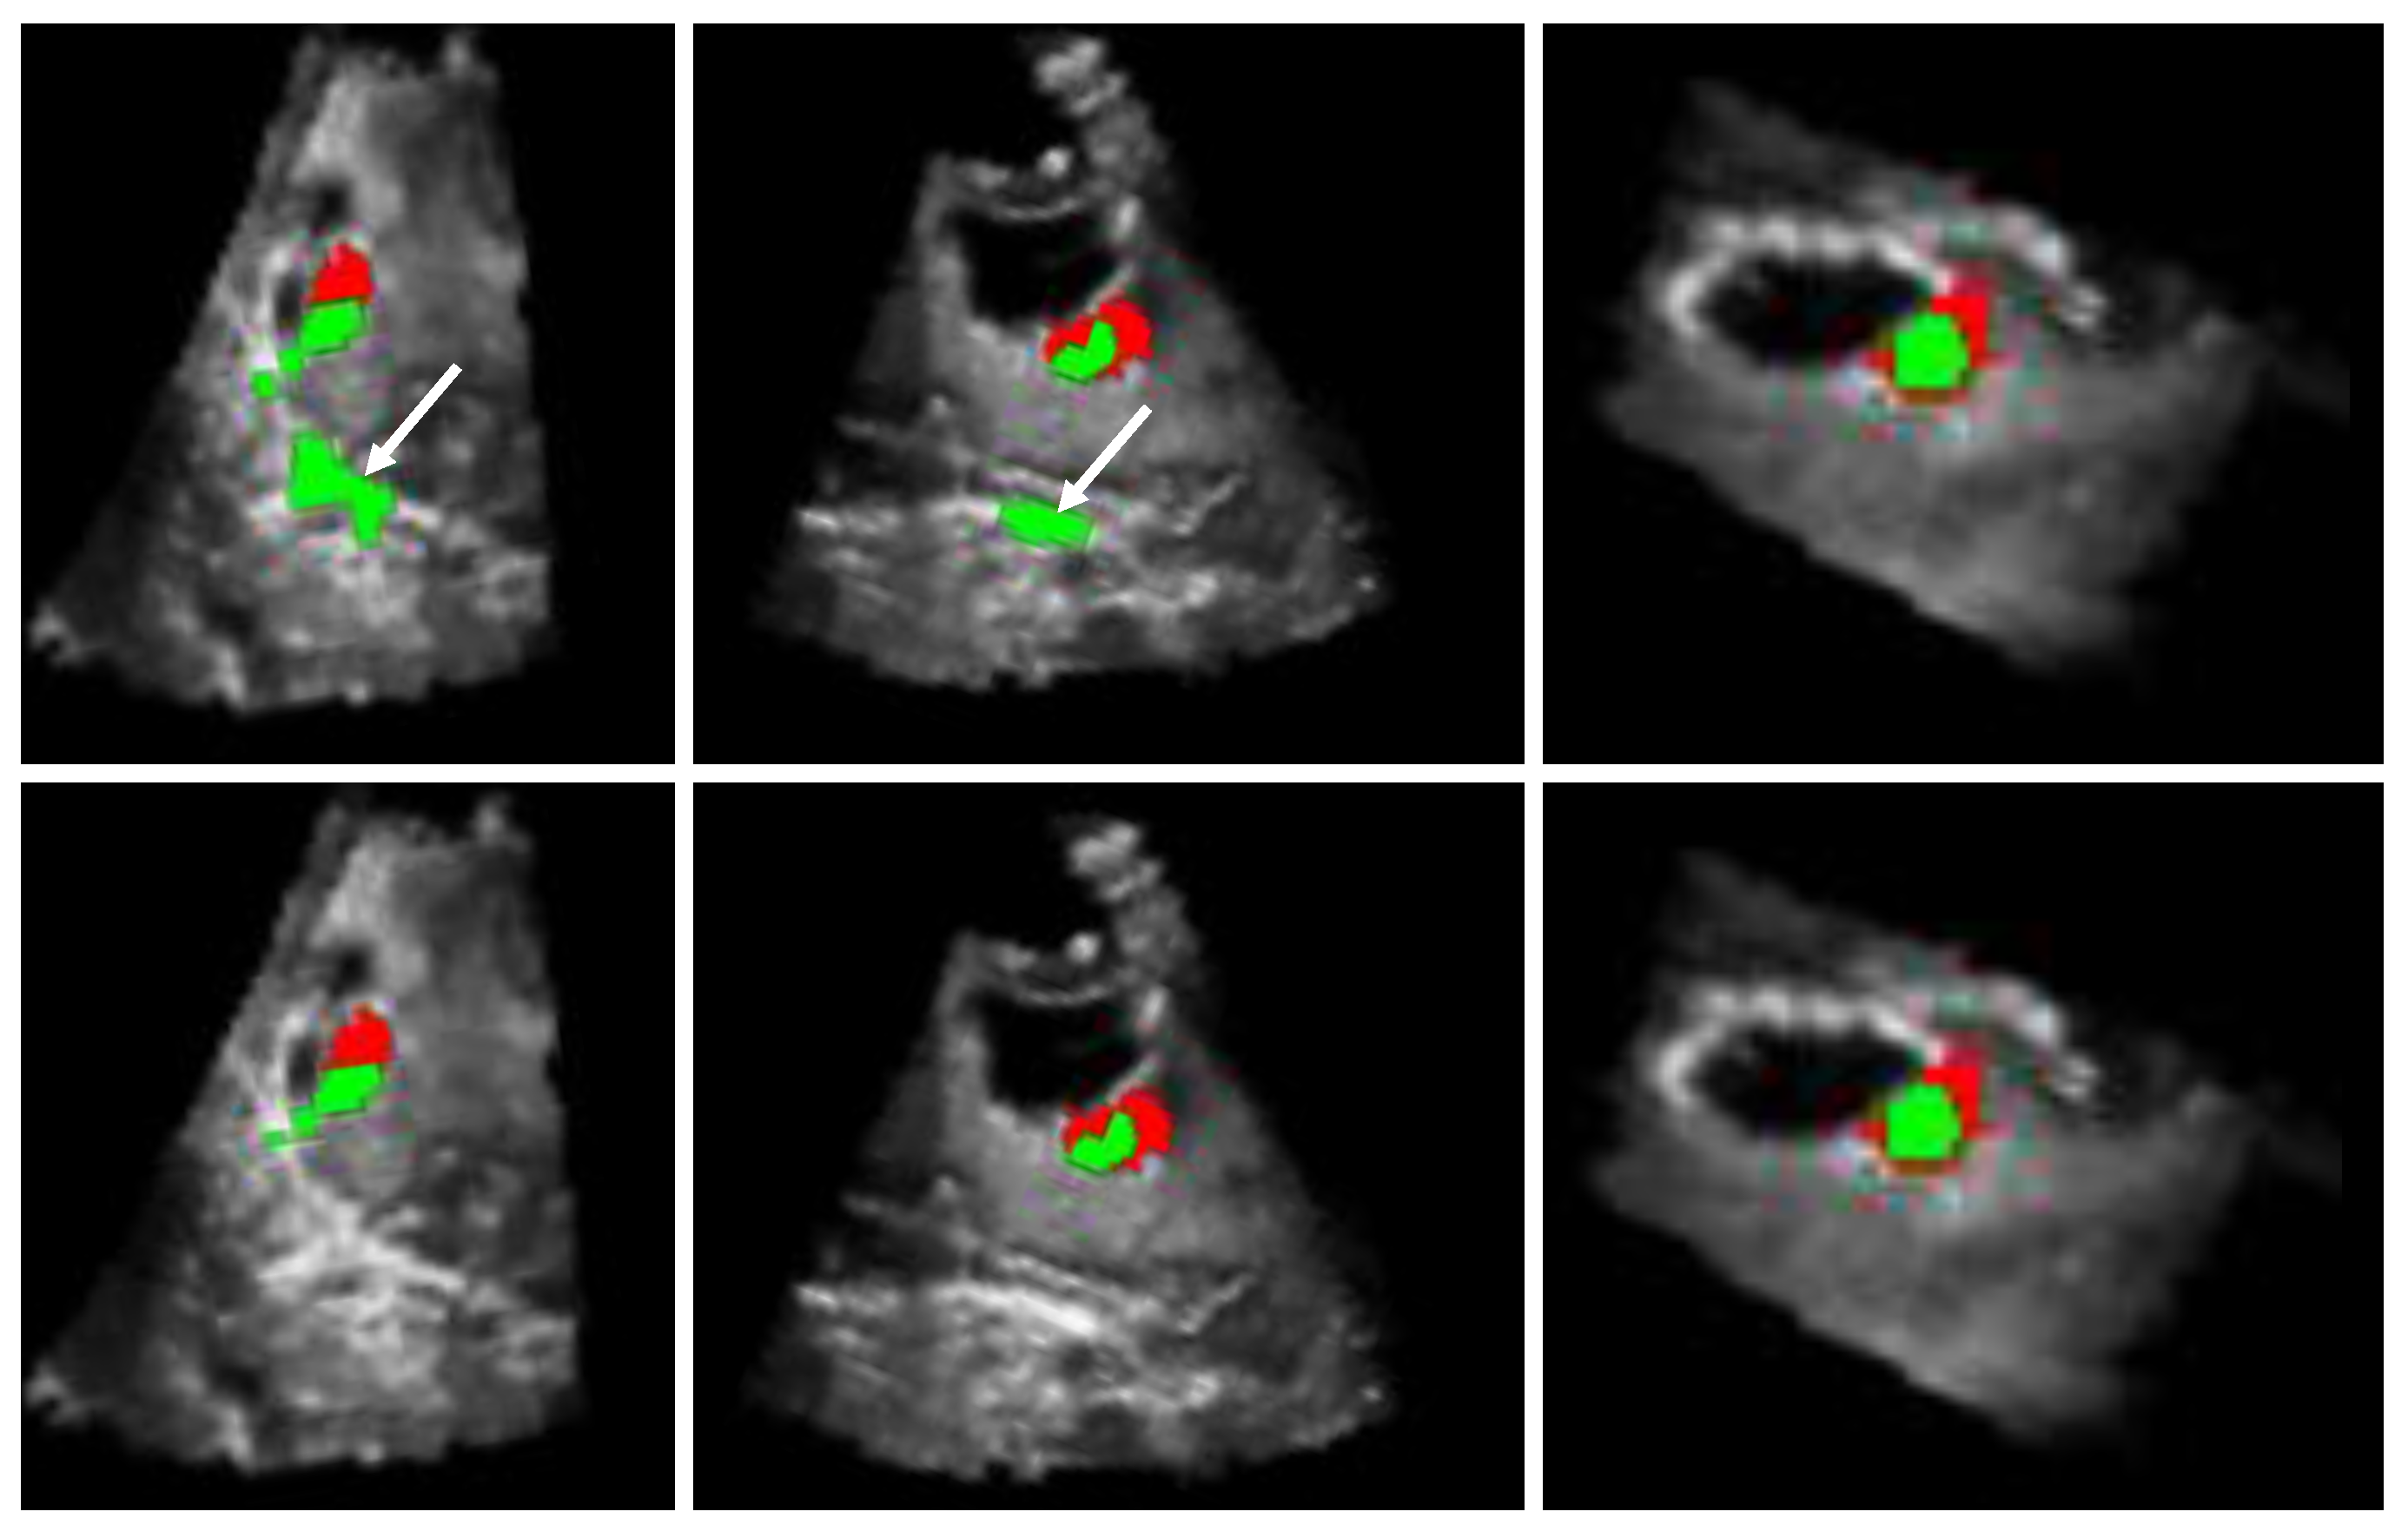

The outcomes, obtained by the automatic proposed method, are presented in Figure 7, Figure 8 and Figure 9. In addition, the algorithm results (in green) and the ground truths (in red) are overlaid on a selected slice of the 3D iB-mode images for visualization purposes. Table 2 summarizes the qualitative and quantitative evaluation. The former is based on expert observations, and the latter is performed by using the overlap, accuracy, area under the curve and error rate measures. The experiments showed that our approach succeeded in detecting the position of all tumor remnant areas in 15 out of 19 patients (). For these cases, a qualitative coding of 1/−1 (all tumorous regions were detected) or 1/1 (all tumorous regions were detected and extra suspected regions, as well) was observed. Regarding the four unsuccessful cases, the areas with tumorous tissue were partially detected in two patients (Patients 2 and 7, where ), and the algorithm failed in the two other cases (Patients 14 and 18, where ). One failure reason is the position of tumor residuals near the image top (Patients 7 and 18). These areas are removed in the preprocessing steps to eliminate artifacts caused by the US probe. The method was also tested on patient data from the set B where false positives were detected in the cases of Patients 20 and 23 and none for Patients 21 and 22.

Figure 9.

Results of residual tumor identification from Patients 13 to 19. The results obtained by using the proposed automatic method (in green) are overlaid with the expert manual segmentation (in red). The algorithm missed completely the target in the case of Patients 14 and 18. In addition, it detected an extra region in the case of Patient 15.